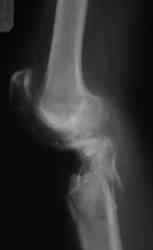

Уважаемые коллеги! На консультацию обратилась женщина, 23 года. В феврале огнестрельное ранение колена. Снимки первичные и майские в приложении. А также внешний вид раны. Укорочения конечности нет. Разгибание в коленном суставе отсутствует. Сгибание сохранено. Нестабильности нет.Дно раны - мертвая кость.

по снимкам у пациентки на данный момент сохраняется дефект наружного мыщелка б\б кости, который со временем приведет к вальгусной дефеормации голени и в настоящий момент практически отсутствует бугристость б\б кости, т.е. зона прикрепления собвственной связки, которую можно в принципе выкроить из средней порции сухожилия 4-хглавой со средней частью надколенника, но сначала необходимо запонить дефект костной ткани, либо путем свободной кости пластики, либо формированием отщепа б\б кости с микродистракцией в КДА Илизарова. т

В клинических снимках вроде достаточно мягких тканей, и возможно закрытие дефекта кожи местным ротационным методом. При возникновении трудностей тогда необходимо применить мышечную пластику. Без

восстановления мягкотканого футляра будут трудности со сращением кости. Мышечную пластику можно совместить с одномоментной кожной пластикой.